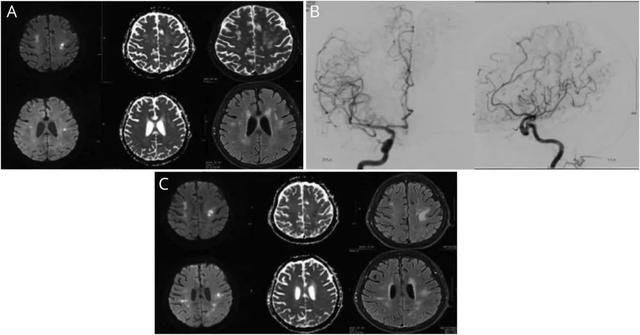

患者为84岁中国女性,因“亚急性认知功能下降3个月,发作性神经功能障碍2天”就诊。患者既往体健,2天内出现了多个单独的局灶性神经系统功能障碍发作(右侧无力伴失语,左侧无力) 。CT血管造影显示大脑中动脉多灶性狭窄和双侧M3段闭塞;后循环未见明显异常。头颅MRI显示双侧额叶和顶叶多发性局灶性弥散受限,弥漫性T2 /Flair信号改变而无异常增强,与梗死相符(图1,A)。患者开始使用小剂量乙酰水杨酸和深静脉血栓预防,并入院进一步诊治。

对于该患者,常规血管造影显示颅内外中小血管呈串珠样改变,提示弥漫性血管病变(图1,B)。血液检查显示炎症标记物升高(红细胞沉降速率115,C反应蛋白56.1),但风湿病学、凝血功能和感染性指标(包括抗磷脂抗体综合征和HIV)检测为阴性。CSF分析显示2个有核细胞,葡萄糖正常为2.3 mmol / L,蛋白质升高为1.46 g / L(正常范围:0.18–0.68),白蛋白升高为0.96 g / L(正常范围:0.14–0.25)。血清和脑脊液中均存在相同的寡克隆免疫球蛋白G条带,提示血脑屏障通透性增加。脑脊液细胞学检查为阴性。胸部、腹部和骨盆CT均未见实体器官恶性肿瘤或淋巴结肿大;副肿瘤抗体阴性。血清和尿液电泳未见明显异常。双侧颞动脉活检仅显示内弹性膜非特异性破坏,不能确定为巨细胞动脉炎(GCA)

图1 患者头颅MRI检查结果。(A)最初的头颅MRI检查显示多灶性卒中。(B)常规血管造影图像显示颅内和颅外血管弥漫性串珠样改变。(C)复查头颅MRI显示新发缺血性卒中和陈旧缺血病灶的进展。

尽管进行了两轮大剂量的类固醇治疗,该患者仍反复卒中发作,复查MRI可见新发缺血性病变(图1,C)。